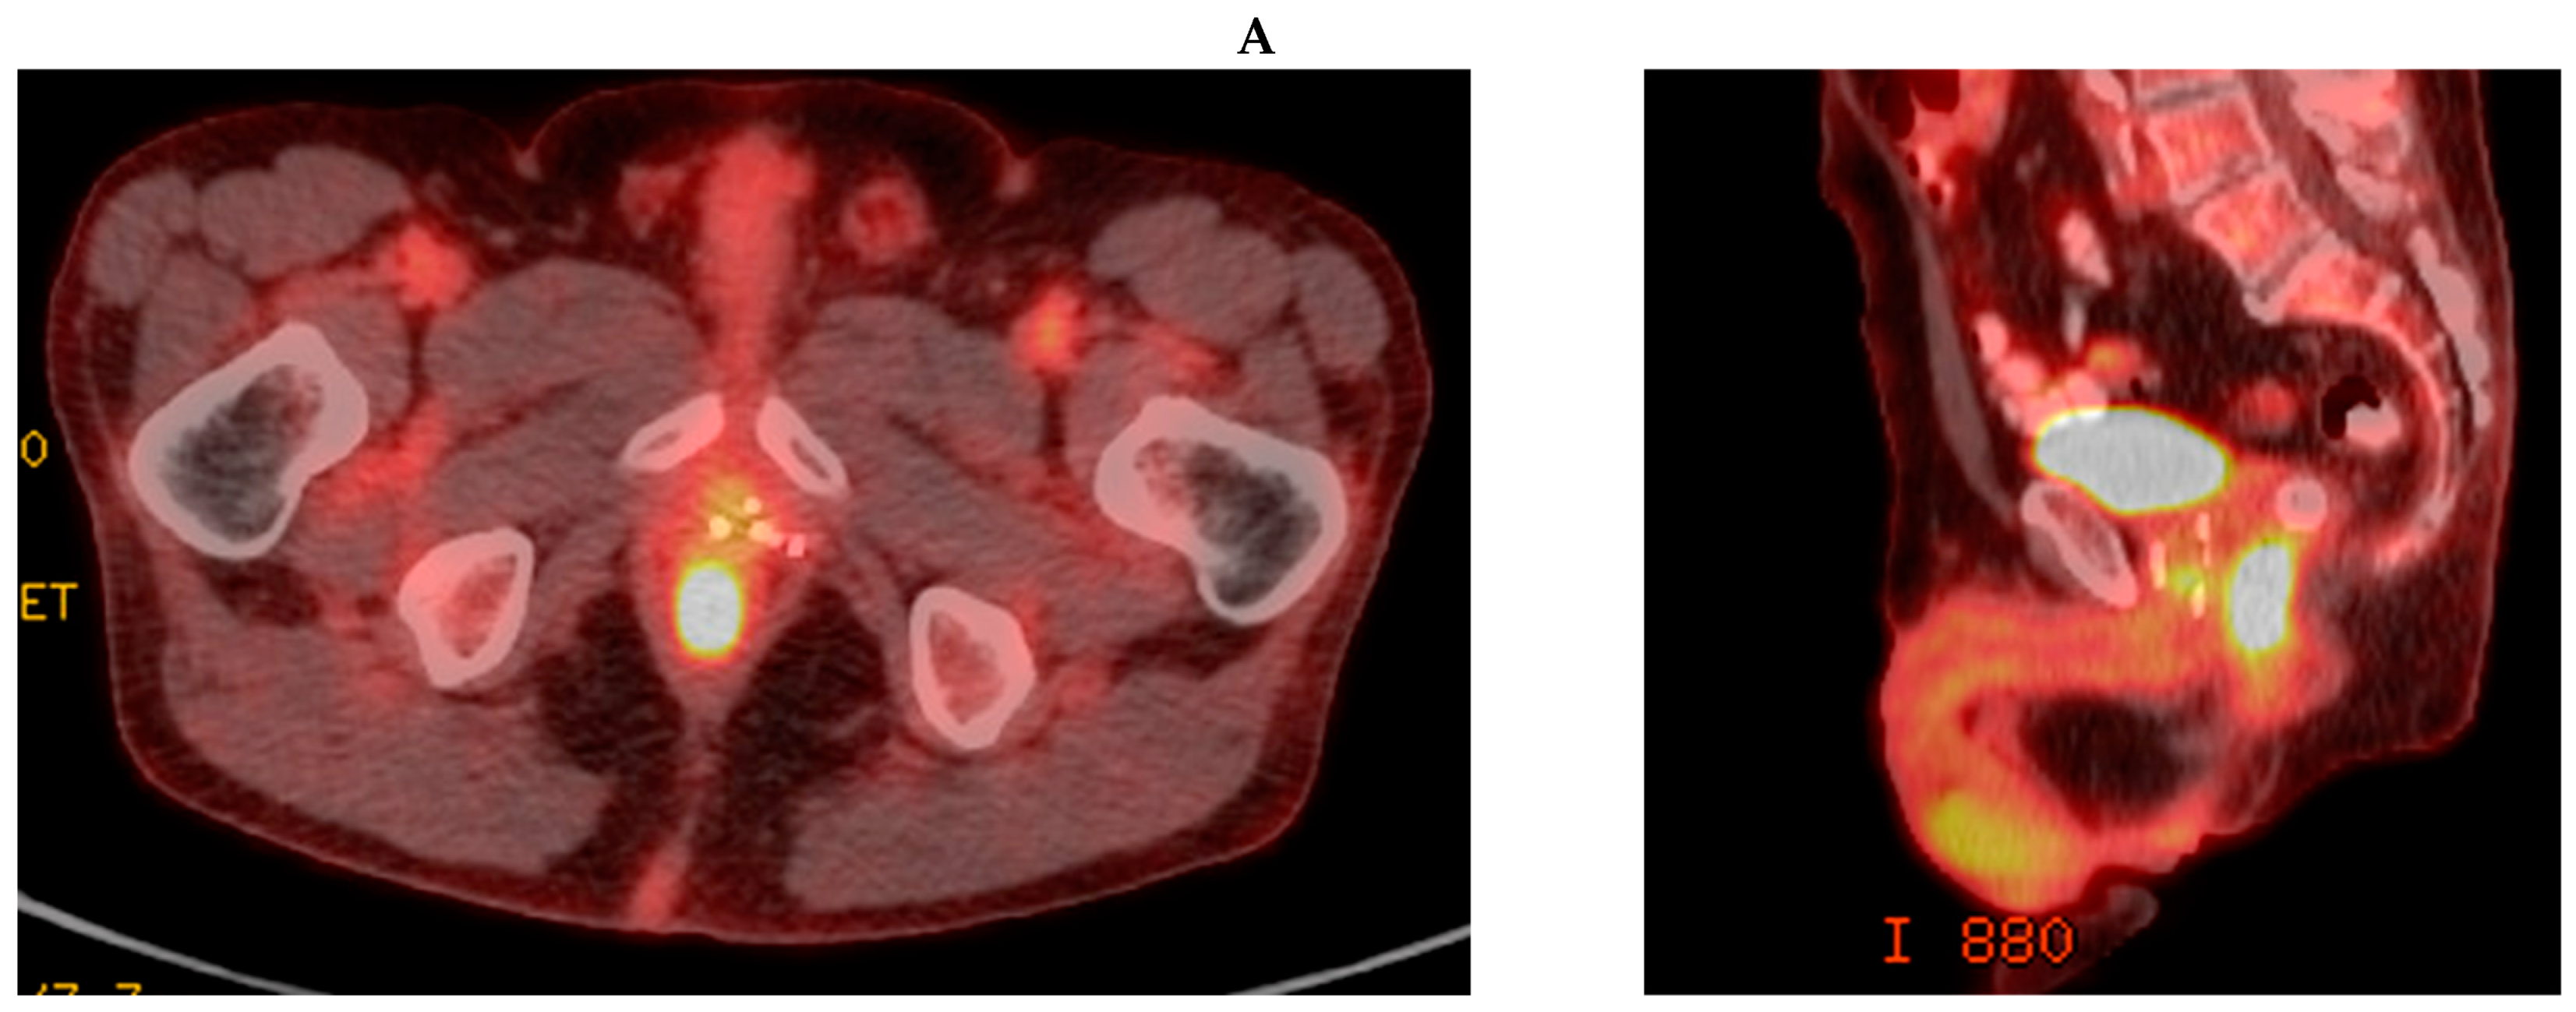

3.1. Case Report 1: Anal Squamous Cell Carcinoma

| Anal | 2006: -LDR | 2018: -Anal canal + LNs 36–48 Gy/24 fx QD | -POD; liver -CR; local | NED | No POD | 2 mo; liver treated with SBRT | 48 mo |

| Disease | GTV V100% | PTV V100% | Mean Rectal Dose (cGy) | Mean Bladder Dose (cGy) | Max Distance of Spacer (cm) |

|---|---|---|---|---|---|

| Anal | 100% | 96% | 4024.7 | 2730.1 | 1.71 |